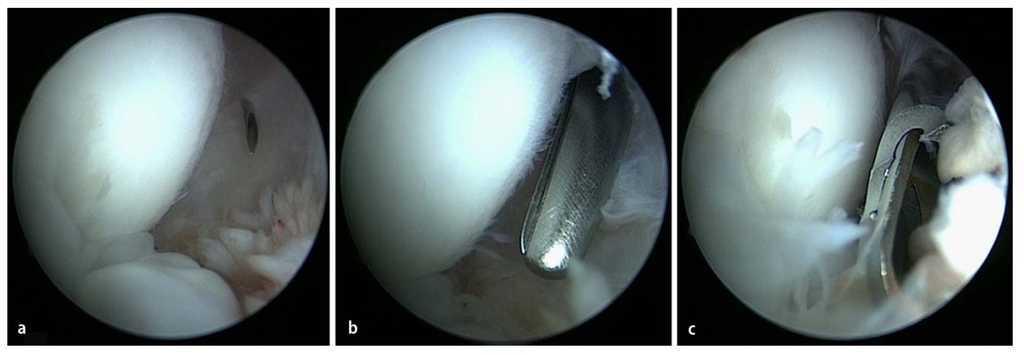

Fig. 15 a) Las formaciones osteofíticas en la zona del olécranon se extraen mediante un pequeño cincel Lambotte (5-6 mm) a través del portal transtendinoso. b) Después de haber desprendido los osteofitos, estos se extraen con una pinza de agarre. Para que la unión sea suave, se puede alisar la zona con un resector sinovial. Para finalizar, se verificará y documentará el rango de movimiento, se introducirá un drenaje de Redon en la articulación y se cerrarán los abordajes mediante una sutura de punto simple.

Fig. 16 Para la documentación de los resultados de la intervención quirúrgica se realiza un control radiológico en dos planos del codo antes del alta del paciente. a, b) Se pudieron extraer los osteofitos humerales presentes en el preoperatorio (flechas).